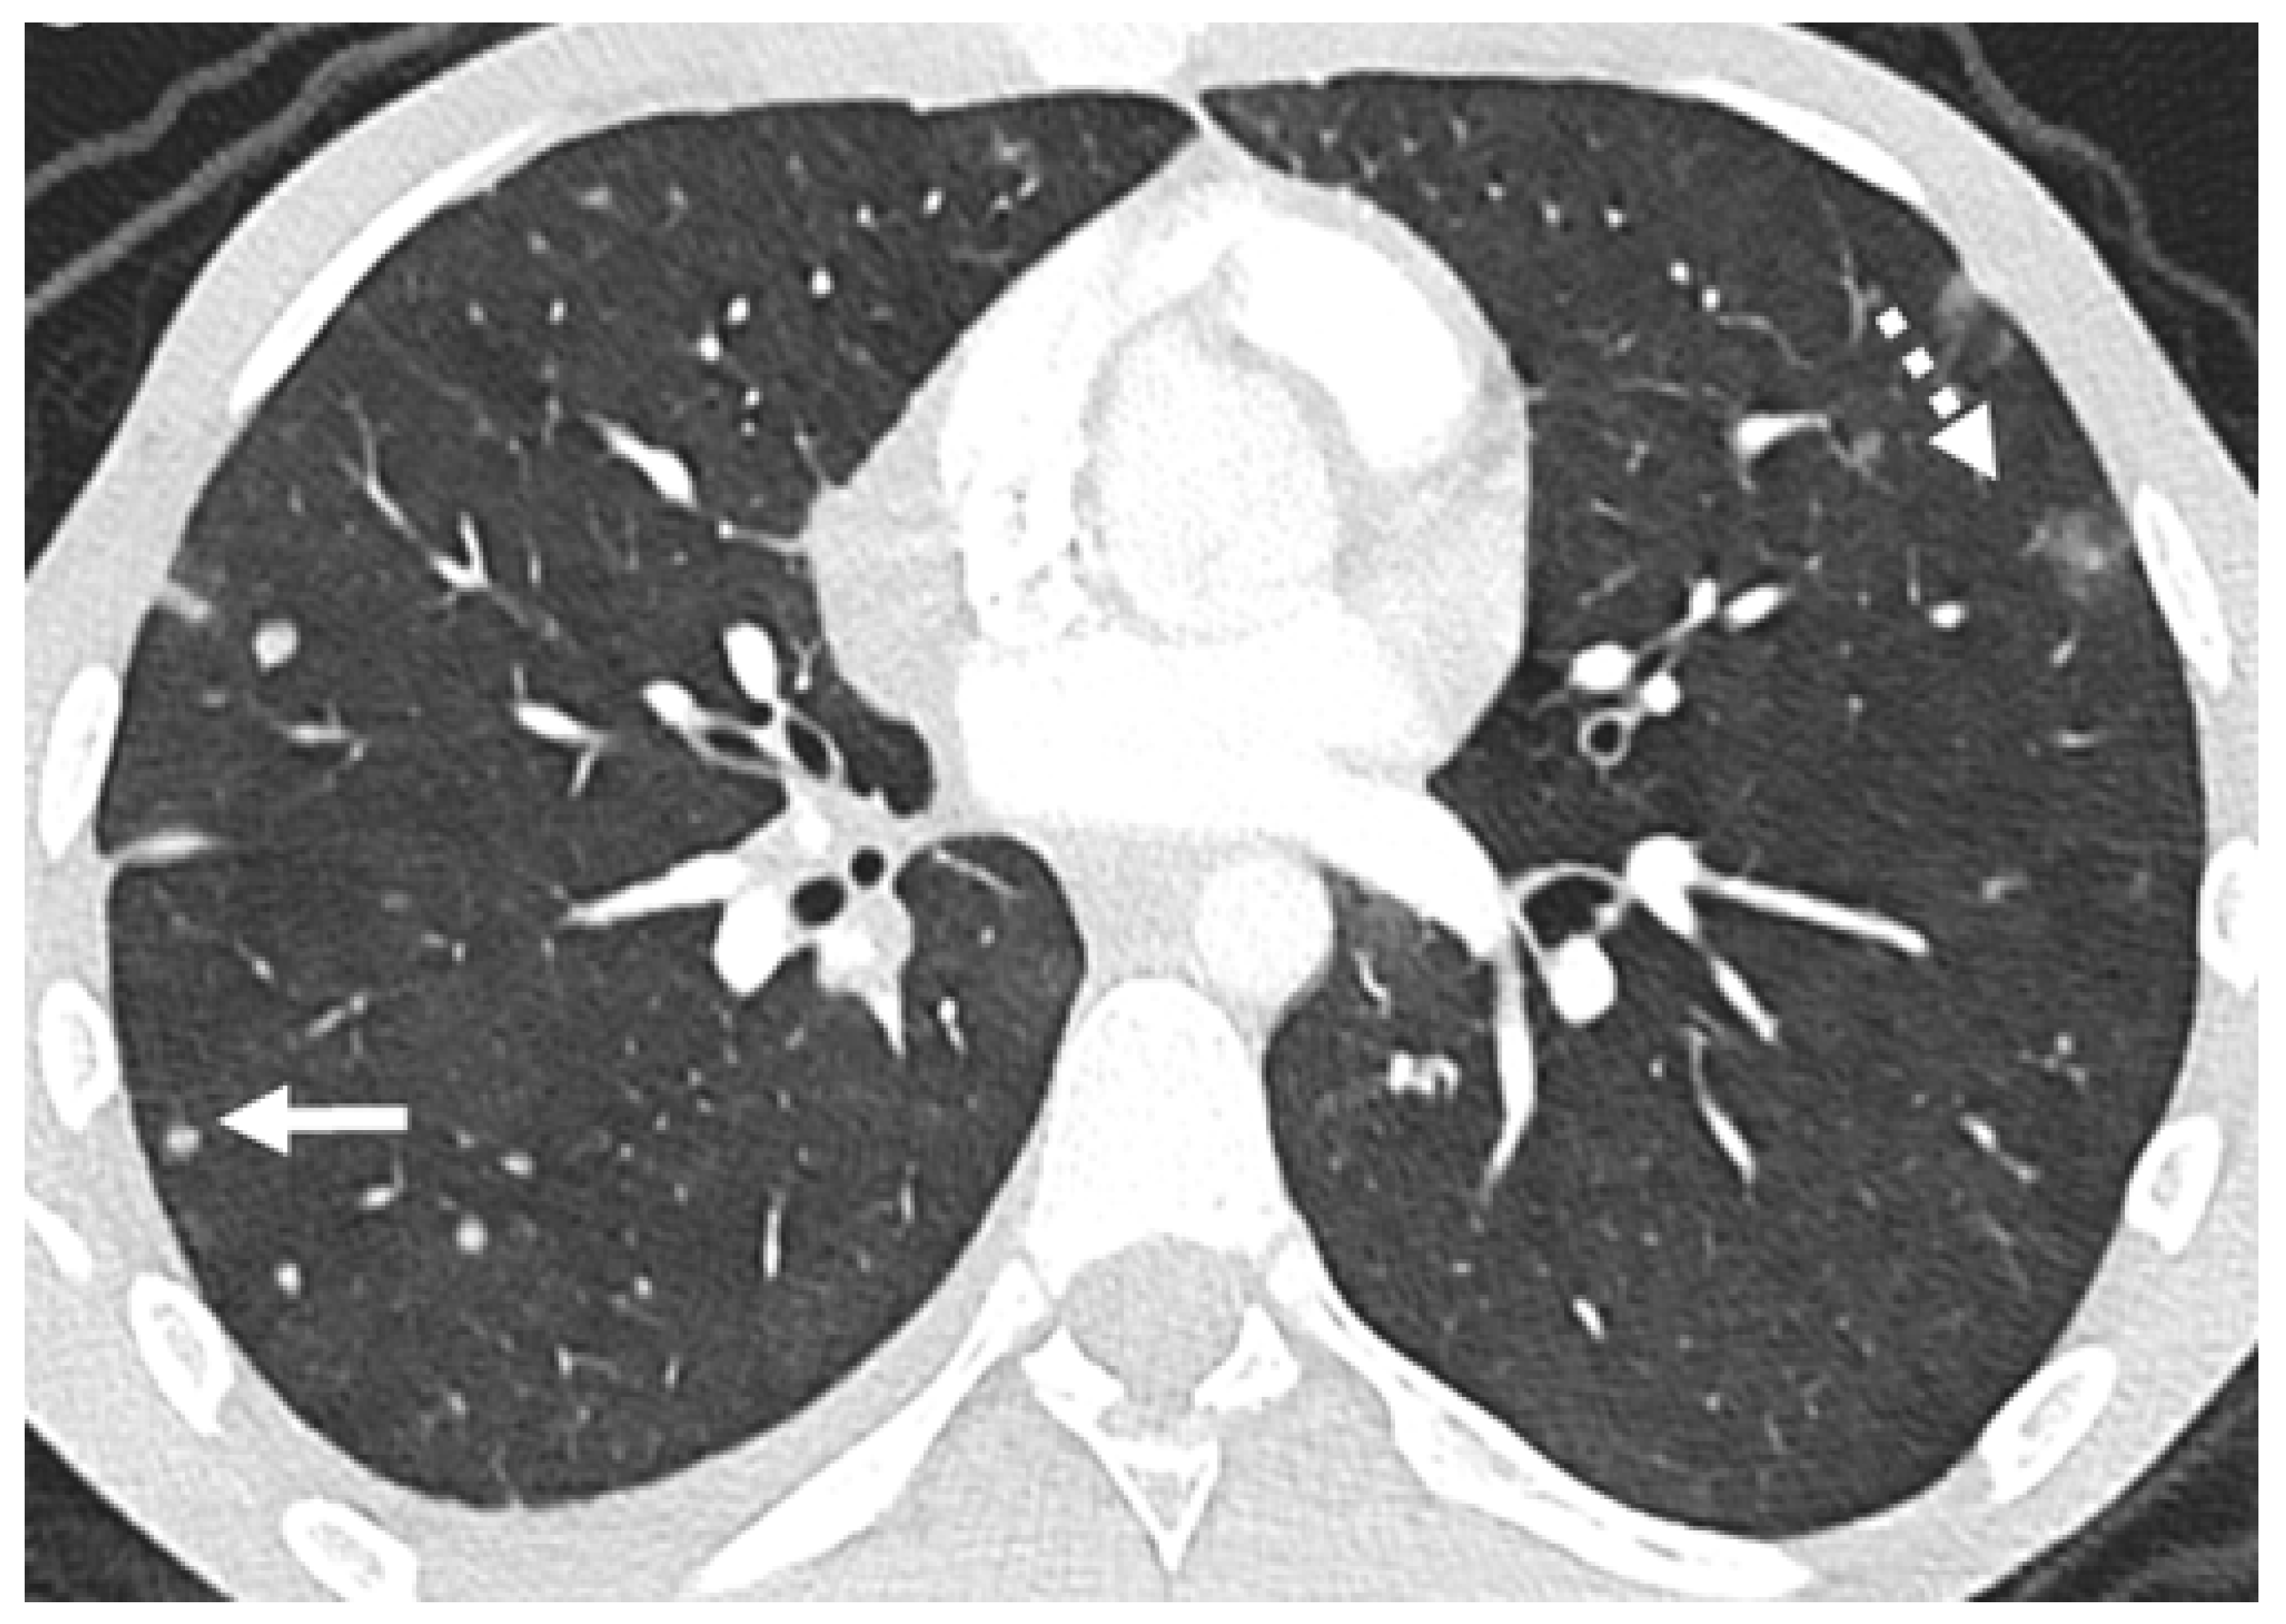

2.1. Parenchymal Metastasis

2.2. Vascular Metastasis